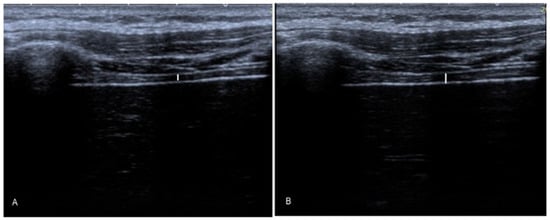

2.5.1. Diaphragm Thickness

- Goligher, E.C.; Laghi, F.; Detsky, M.E.; Farias, P.; Murray, A.; Brace, D.; Brochard, L.J.; Sebastien-Bolz, S.; Rubenfeld, G.D.; Kavanagh, B.P.; et al. Measuring diaphragm thickness with ultrasound in mechanically ventilated patients: Feasibility, reproducibility and validity. Intensive Care Med. 2015, 41, 642–649. [Google Scholar] [CrossRef]

- Calvo-Lobo, C.; Almazán-Polo, J.; Becerro-de-Bengoa-Vallejo, R.; Losa-Iglesias, M.E.; Palomo-López, P.; Rodríguez-Sanz, D.; López-López, D. Ultrasonography comparison of diaphragm thickness and excursion between athletes with and without lumbopelvic pain. Phys. Ther. Sport 2019, 37, 128–137. [Google Scholar] [CrossRef]